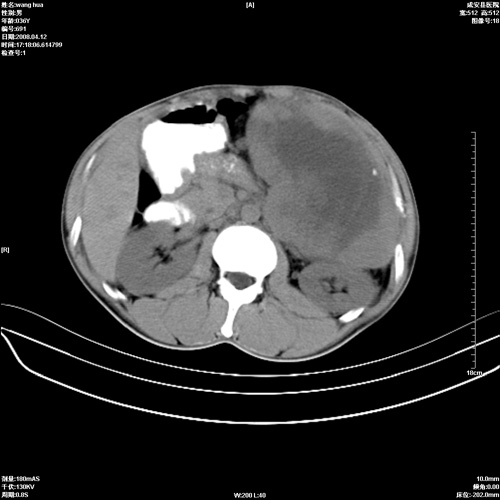

标题: CT12809:男36岁,自感上腹胀5天,B超诊断为脾肾之间占位,血 [打印本页]

标题: CT12809:男36岁,自感上腹胀5天,B超诊断为脾肾之间占位,血

请各位老师先分析一下定位 明天做增强

脾脏病变,密度不均,可见钙化,考虑脾血管瘤,建议增强

脾脏明显增大,其内见巨大低密度灶,境界不清,病史较短,考虑恶性病变脾血管内皮细胞肉瘤可能。建议增强扫描与脾脏淋巴瘤及血管瘤鉴别。